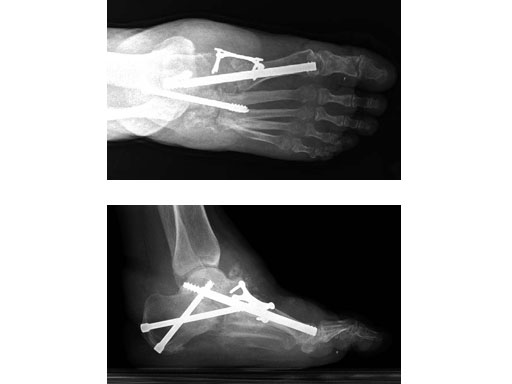

Case 2: 48-year-old male

Case provided by Andrew K Sands, New York, USA

Charcot foot treated with MFB and X-plate.